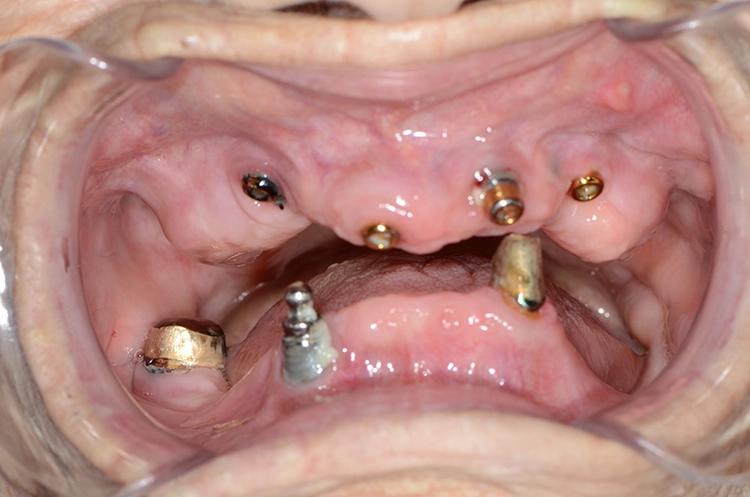

Bei den meisten alltäglichen Tätigkeiten wie Körperpflege und Kochen gaben die 100-Jährigen an, Hilfe zu benötigen. Obwohl offensichtliche Defizite in der häuslichen Mundhygiene vorlagen, wie generalisiert harte und weiche Beläge, schlecht gereinigter herausnehmbarer Zahnersatz, Druckstellen usw., gaben nur 7 (12,7%) der 100-Jährigen an, hierbei Hilfe zu benötigen. Die Abbildungen 1 bis 3 zeigen beispielhaft die klinische intraorale Situation von 3 100-Jährigen, die an der Untersuchung teilgenommen haben.

Es konnten Daten zur Periimplantitis an n = 27 Implantaten erhoben werden. Die Ergebnisse sind in Tabelle 4 dargestellt. 7 100-Jährige hatten Implantate, entweder in Kombination mit herausnehmbarem Zahnersatz (n = 3, von denen 2 zahnlos waren) oder mit festsitzendem Zahnersatz (n = 4).

Die mittlere Anzahl der Implantate betrug 4,3 ± 3,5. Tabelle 4 zeigt die periimplantären Ergebnisse. Von 27 untersuchten Implantaten wurde die Mehrheit als gesund eingestuft, 29,6% hatten eine periimplantäre Mukositis und 11,1% hatten eine Periimplantitis.